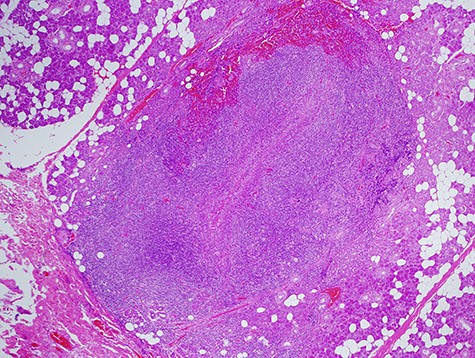

In the histological report, only fibrous scar was found without a sign of fistula or epithelial cells (Fig. 4).

Histological specimen showing the string-like structure. No epithelial cells were observed by the pathologists.